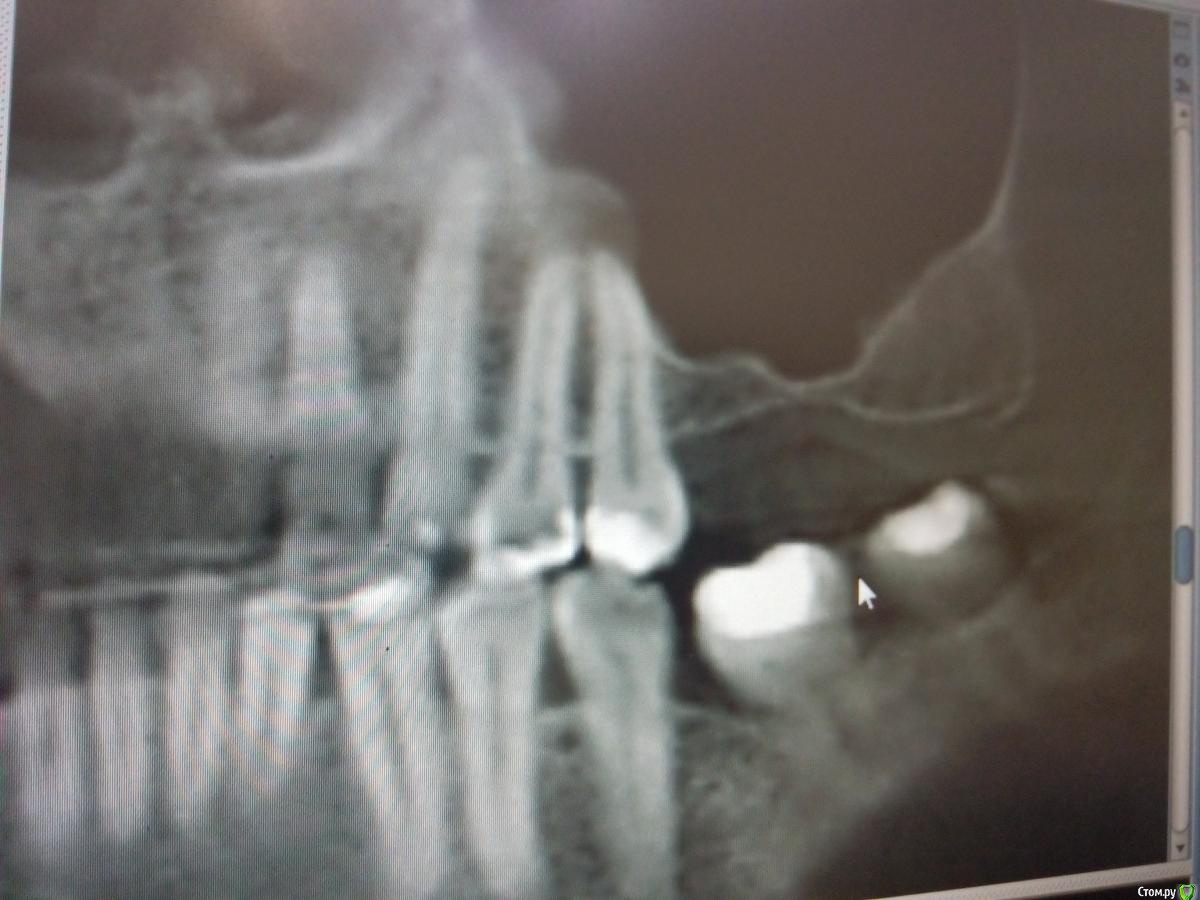

Sampson Опубликовано 14 августа, 2018 Поделиться Опубликовано 14 августа, 2018 (изменено) В феврале провел первый свой открытый синус.Снимок доПосле операцииНеделю назад пришла на контроль. Изменено 14 августа, 2018 пользователем Sampson Ссылка на комментарий

Bier Опубликовано 14 августа, 2018 Поделиться Опубликовано 14 августа, 2018 согласен с Колесниковым, медиально надо было шире значительно. Теперь даже позиция имплантата не очень то выходит.. В натяг попадаете в медиальный край аугментата. Ссылка на комментарий

pit Опубликовано 14 августа, 2018 Поделиться Опубликовано 14 августа, 2018 Из этого случая надо просто сделать вывод и впредь делать доступ медиальнее и протяженнее. Или 2 окна. В данном случае я бы установил имплантаты в центр аугментата и в позицию "полвосьмого" зуба и сделал бы 3 коронки. 26 зуб - консольная единица, отмоделировал как премоляр. Лучшее объяснение больному, на вопрос: "почему 3 коронки?" - в необходимой позиции не выросла костная ткань, поэтому имплант ставится дальше от 25 зуба и если делать 2 коронки, как запланировано, то постоянно будет забиваться пища и это будет невыносимо противно) 1 Ссылка на комментарий